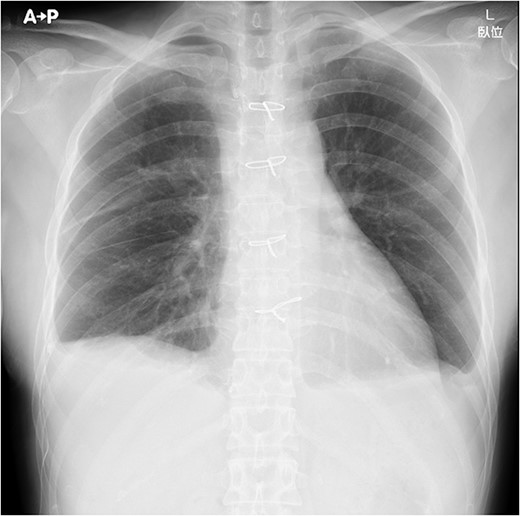

Under general anesthesia, she underwent total thymectomy via median sternotomy. Her post-operative course was uneventful and there was no visible chyle leakage from the chest drainage tube. On post-operative day 2, the chest drainage tube was removed. The chest X-ray on post-operative day 7 revealed no massive pleural effusion (Fig. 2), and she was discharged on the day. The final pathological diagnosis was a Type A thymoma with Masaoka’s Stage I.

Chest X-ray on post-operative day 7 revealing no massive pleural effusion.